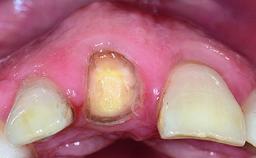

Replacement of an Ankylosed Upper Left Central Incisor: Bone Augmentation and Socket Grafting, Late Placement of an RC Bone Level Implant

A 15-year-old male patient was referred to us by his pediatric dentist in June 2004 for evaluation of treatment options for his failing tooth 21. The patient had recently seen an endodontist for internal bleaching and been advised that there had been significant resorption and ankylosis. The patient’s mother was concerned because the tooth appeared shorter than the adjacent one. His past dental history was significant for trauma (September 2001), where the tooth had been avulsed and reimplanted. Teeth 11 and 21 had been endodontically treated.

Soft Tissue Anatomy Intact Defective

Bone Volume Horizontally and vertically sufficient Horizontally deficient Deficient vertically or deficient vertically AND horizontally